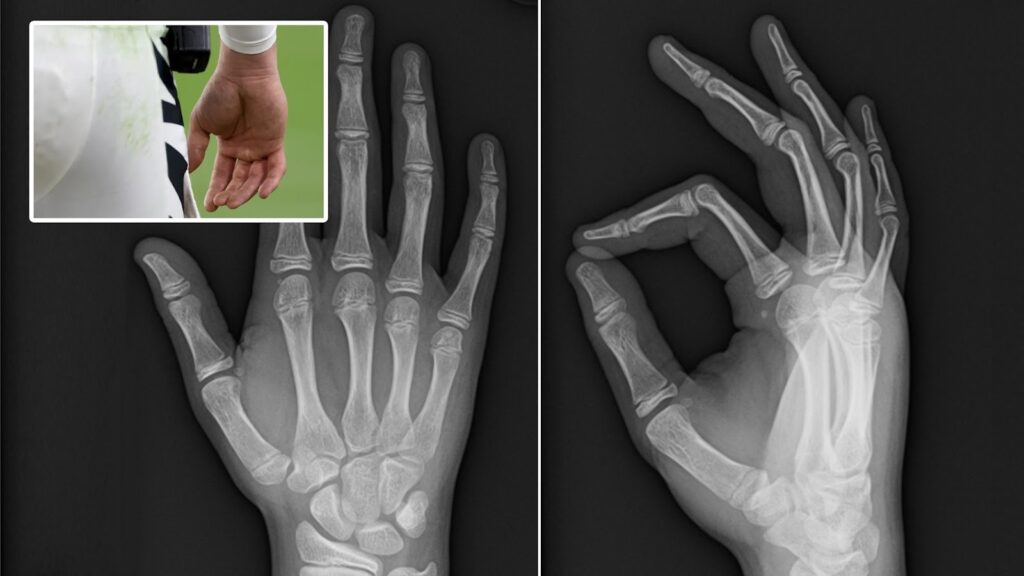

November 2023 brought another challenge. In a Thursday night game against the Ravens, Burrow tore a ligament in his right wrist after an awkward throw. He left the game early, and surgery followed, ending his season. This Joe Burrow injury was particularly tough because it affected his throwing hand – the tool of his trade.

Dangling modifier aside, recovering from wrist surgery, Burrow dove into therapy with determination. Sessions included grip strengthening and range-of-motion exercises. By 2024, he was back, and reports showed no lingering issues. His performance that year proved the rehab worked wonders. Experts say such injuries, when handled properly, can lead to even better mechanics. Burrow’s case is a prime example of turning adversity into opportunity.

Capturing a moment of vulnerability on the field, this photo reminds us of the human side of athletes, but also their ability to rise again.